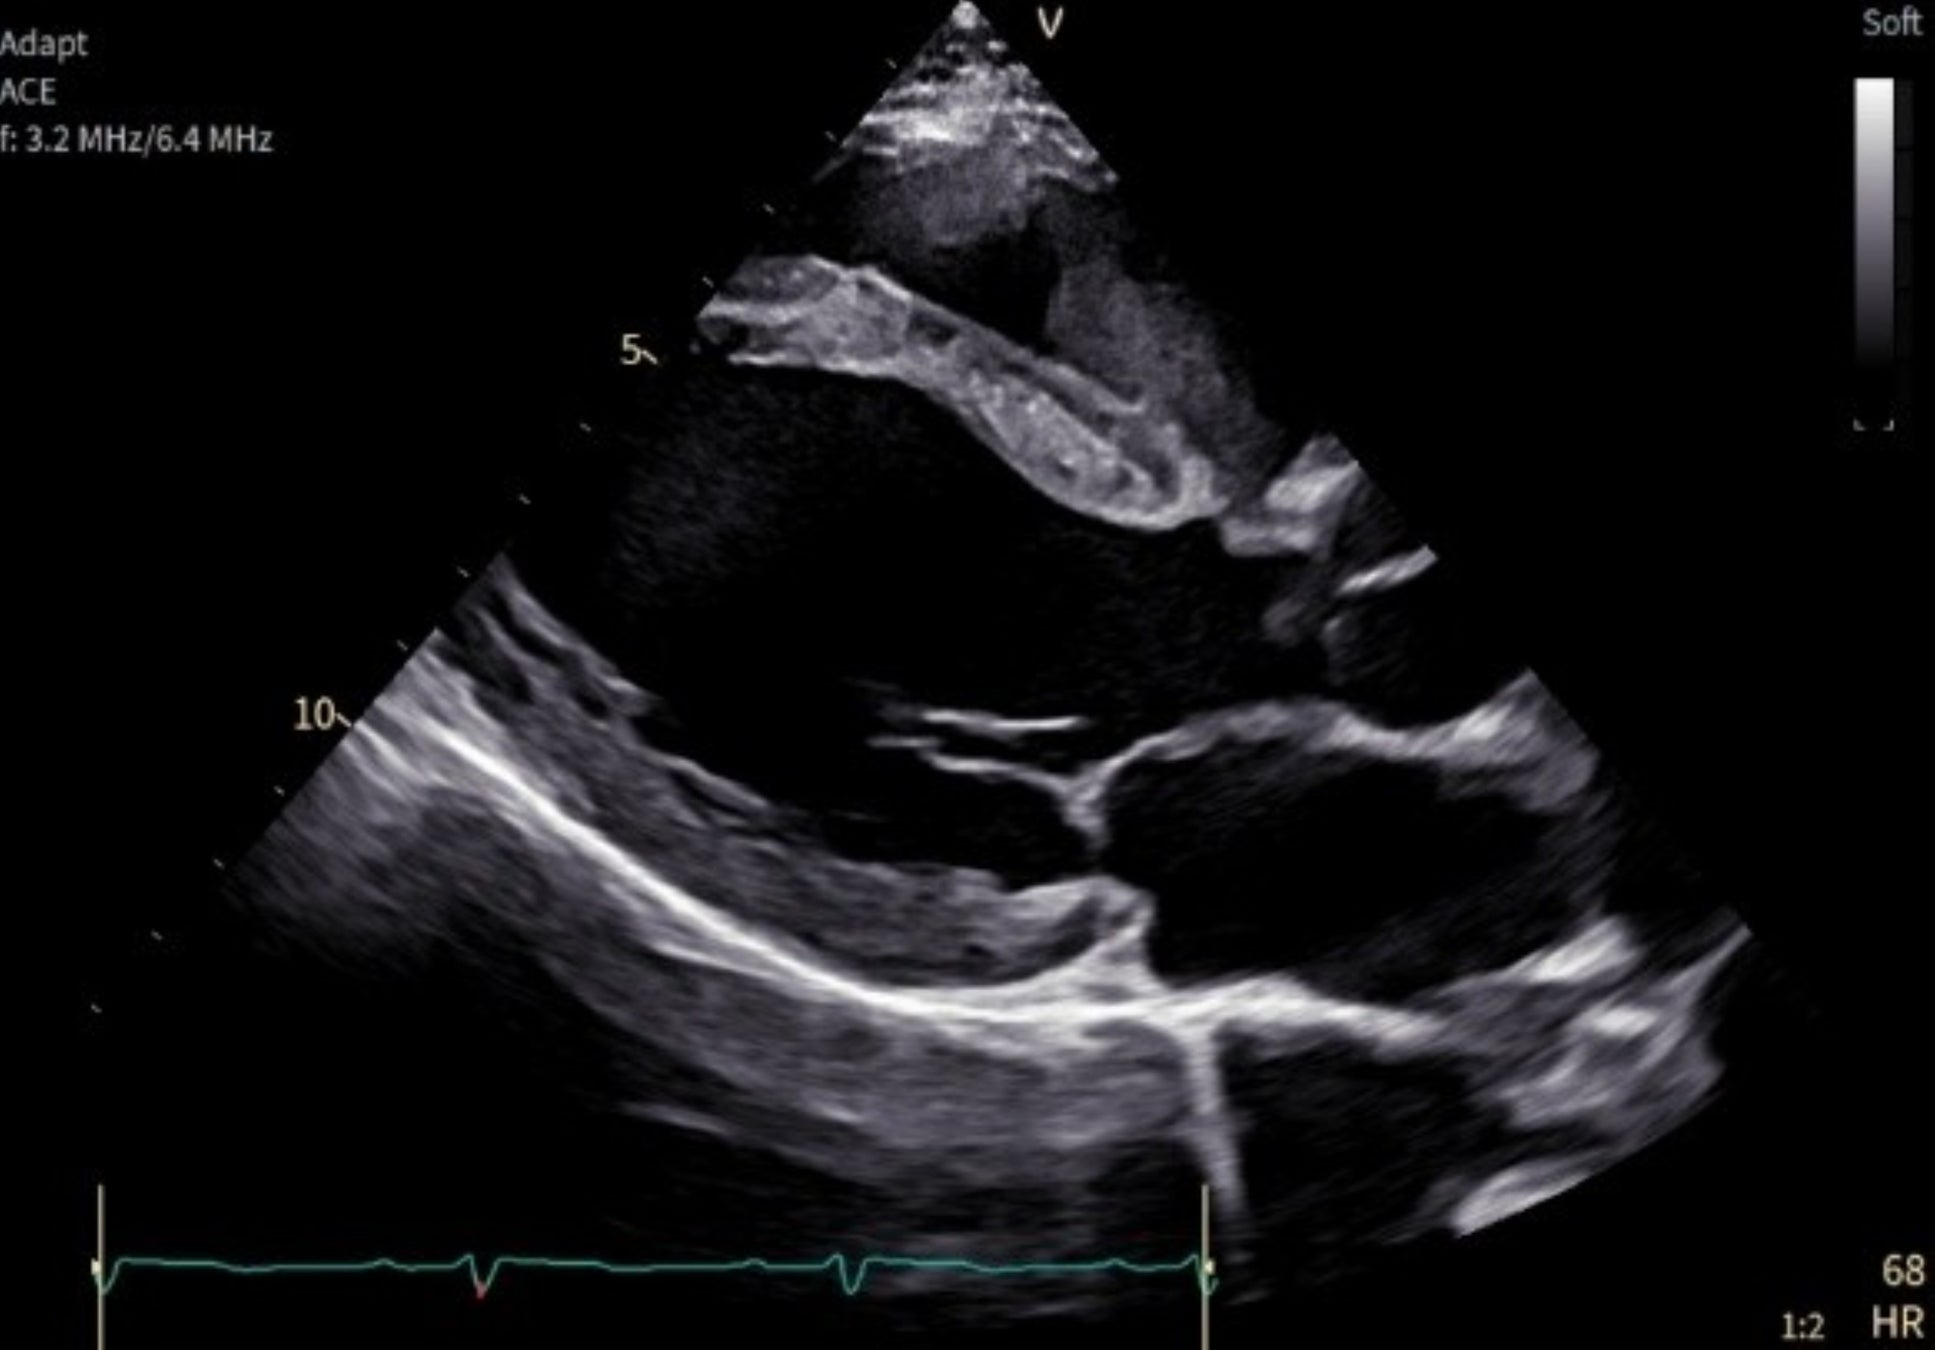

「Vivid Pioneer」は「Vivid」シリーズを11年ぶりに刷新した心臓領域の最上位機で、画質向上と新たに搭載されたAI補助機能により効率性の向上を目指します。なお、GEヘルスケアは3月20日より開催される第90回日本循環器学会学術集会にて本製品を初展示いたします。

「Vivid Pioneer」は、これまで検査者が手作業で行っていた血流解析をAIが自動で行い、短時間で安定した測定プロセスを提供します。また、心臓の主要な部位(左心室と左心房)の動きや形を三次元で自動分析し、検査者間の標準化を支援します。そのほか、次世代の画像エンジン機能により、細部の見やすさ(空間分解能)や色の見やすさ(カラー感度)が向上し、より高精度な心臓の立体画像を描出します。

「Vivid Pioneer」は、検査室や病室など限られたスペースにも適するようコンパクトに設計され、超音波画像診断装置に最適な大型モニターも備えています。またユーザーインターフェイスもシンプルで直感的に操作できるよう刷新されました。加えて、バッテリー搭載が可能となり、電源を抜いても検査を継続することや、停電時でも最大5分間スキャンすることができます。そのほか、プローブは広帯域の周波数を使用し幅広い年齢層やさまざまな体格の患者さんに対応し、心臓の微細構造を鮮明に描出します。